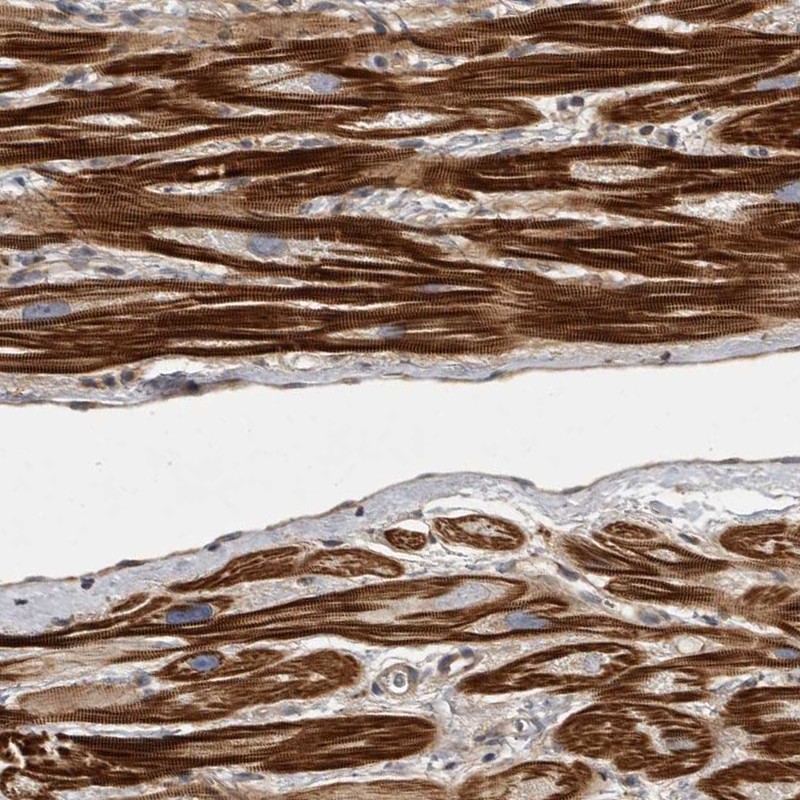

Immunohistochemical staining of human heart muscle shows strong cytoplasmic positivity in myocytes.